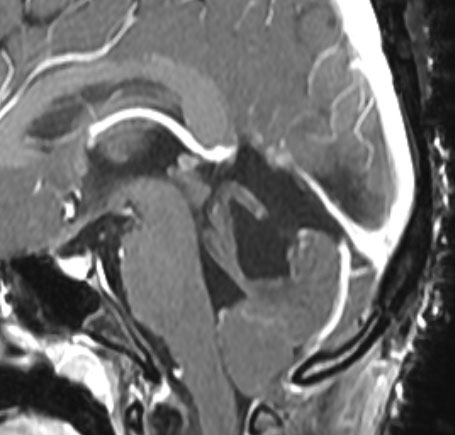

左は術前,右は手術直後のMRIです。このビデオを見て,およその手技の順番のみ把握して下さい。

松果体腫瘍へのOTAのルートです。occipital transtentorial apporachというのは黄色の矢印に沿ってガレン大静脈の下に入る方法であり,そこから松果体部を通って第3脳室内へ直線的な視野が展開します。

もし,このように矢状洞が左に寄っているタイプであれば,右後頭開頭をして,右の後頭極を牽引して,大脳半球間裂の右側から入った方が有利です。理解しやすいように左右反転していますので,MRIは左右逆でみてください。